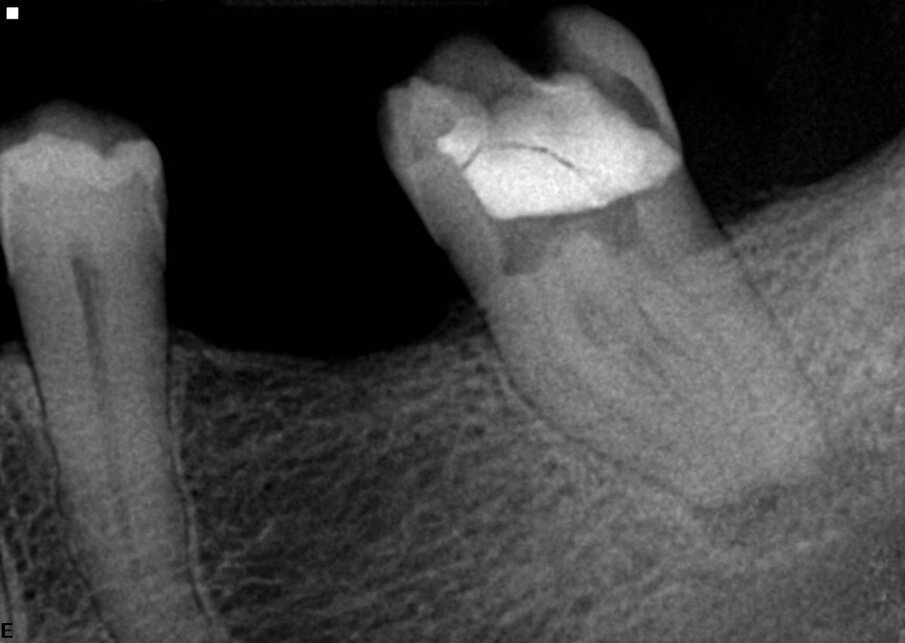

Sledeći primer je takođe bio direktan slučaj. Ovo je bio maksilarni lateralni sekutić sa nekrotičnom pulpom i blago resorbovanim vrhom. ZenFlex turpija 55/0.06 korišćena je u tehnici sa jednim instruemntom za lečenje ovog kanala (Sl. 3).